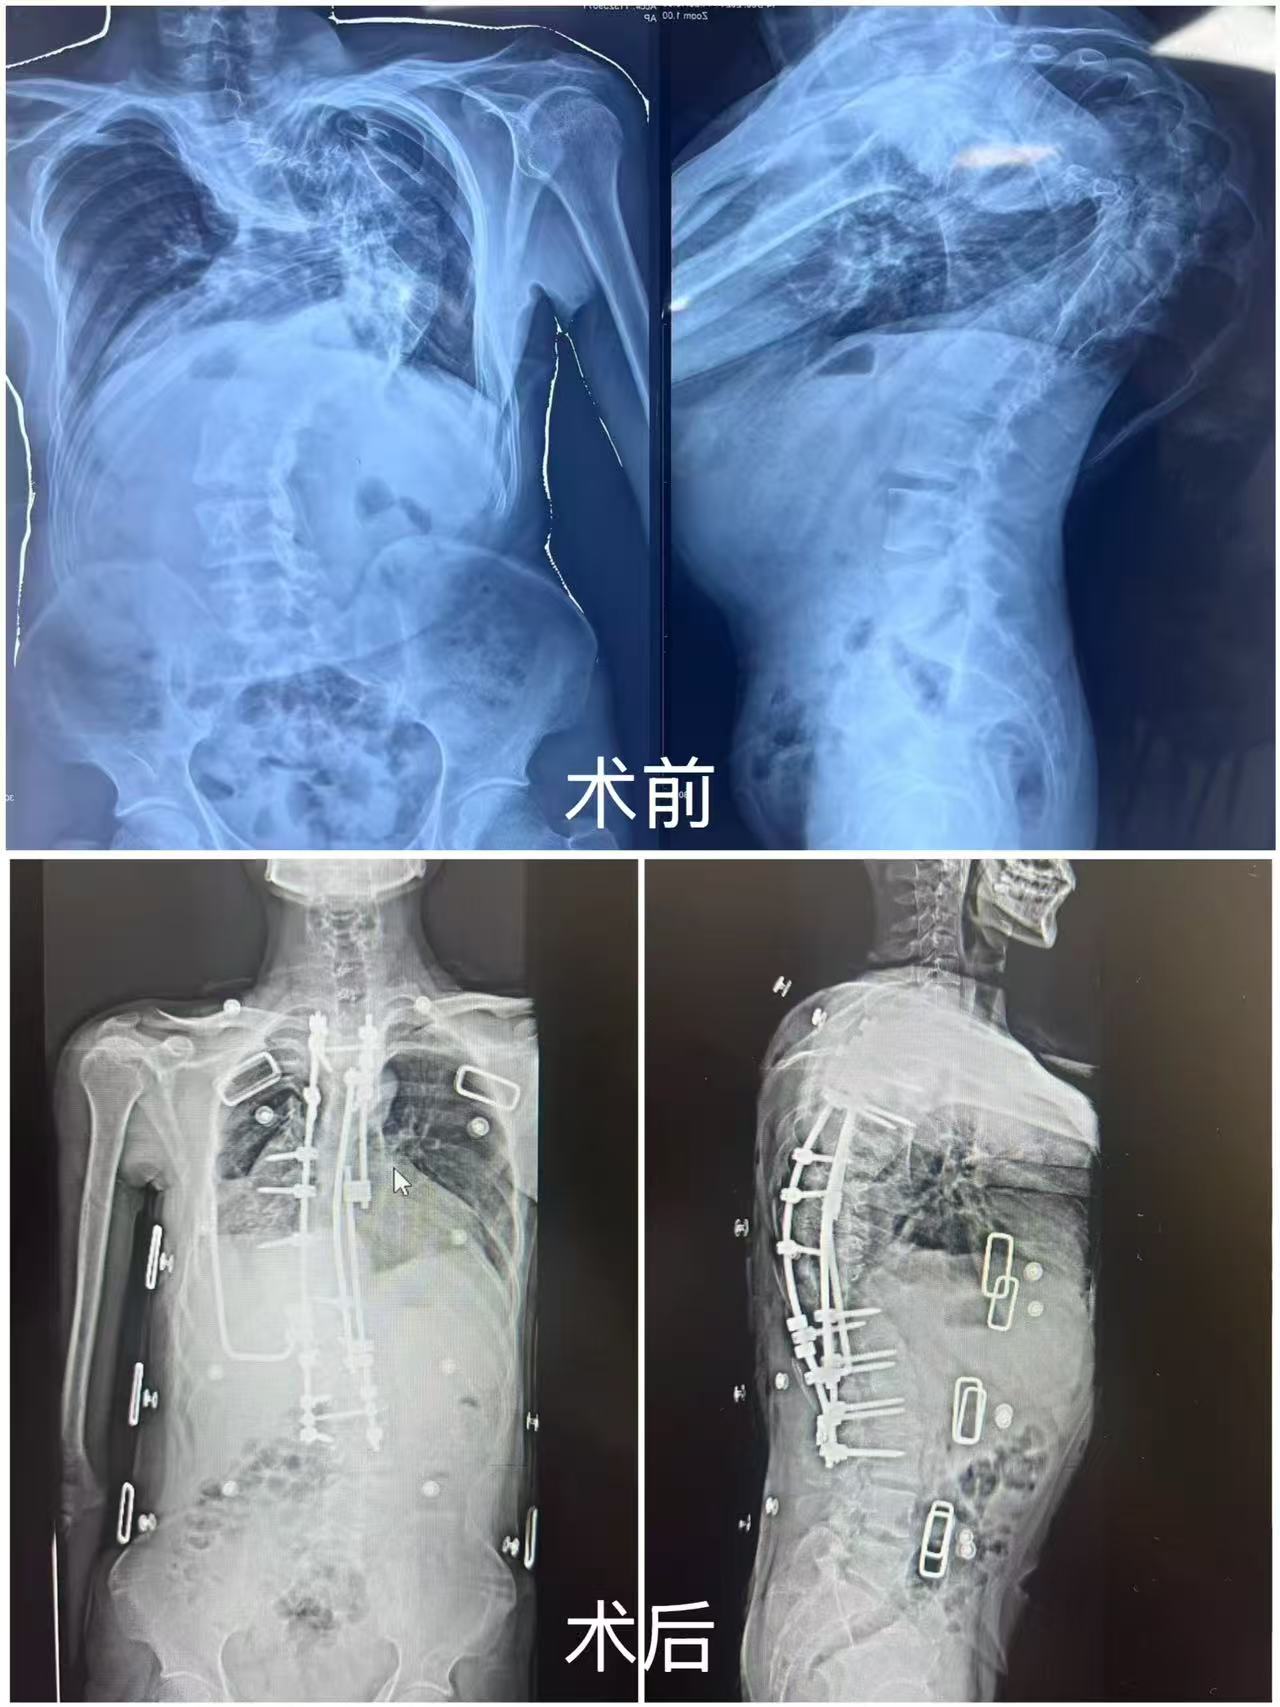

31岁的昌都小伙绕吉(化名)因极重度脊柱侧弯后凸畸形,背后隆起一个接近180度的“驼峰”。近日,在重庆医科大学附属第二医院(以下简称“重医附二院”)脊柱外科矫形团队的帮助下,他终于实现了“挺直脊背”的夙愿,身高也从术前的167厘米增长至183厘米。

检查结果显示,绕吉的脊柱侧弯已近180度,脊髓严重受压、紧贴椎弓根,胸廓畸形持续压迫心肺。该院脊柱外科副主任楚磊教授称,如此严重的畸形若直接手术极易损伤脊髓,风险极高。经反复讨论,团队决定先进行头盆环牵引治疗——在头部与骨盆安装支架,通过缓慢持续牵引拉伸脊柱,增强脊髓耐受性,同时进行肺功能训练,为手术做准备。

手术当天,团队奋战9小时。他们细致分离粘连组织,在严重旋转的椎体中精准植入17颗螺钉,切断12根变形肋骨,并植入U形棒稳定胸廓……每一步操作都如履薄冰,却又冷静而稳健。医生们长时间保持固定姿势,汗水湿透手术衣,但无人松懈——他们甚至,手中托着的是绕吉三十年的期盼。

术前、术后CT对比

此次手术是重庆首例成功实施的180度极重度脊柱畸形联合矫正手术,不仅是医学技术的突破,更是一次生命重建,彰显了重医附二院在该领域的综合实力。每一例重度畸形患者的治疗,都是对医学极限的挑战。未来,团队将继续深化“脊柱—胸廓—心肺”整体治疗模式的探索,助力更多“折叠人”挺直脊梁、拥抱新生。